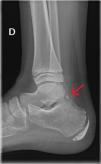

Varón de 11 años, valorado por dolor en el tobillo derecho de 3 días de evolución, sin traumatismo desencadenante. Practicaba fútbol ocasionalmente. Refería dolor en la inserción del tendón de Aquiles, con pinchazos reproducibles con la marcha. No dolor ni inflamación a otros niveles. Exploración física anodina. En la radiografía del tobillo (fig. 1) se objetivó un hueso adicional, el trígono, conocido como «os trigonum» (OT).

El trígono es un hueso accesorio, congénito, presente en el 14-25% de los astrágalos, uni- o bilateralmente, detrás del astrágalo, conectado al mismo, mediante una cinta fibrosa.